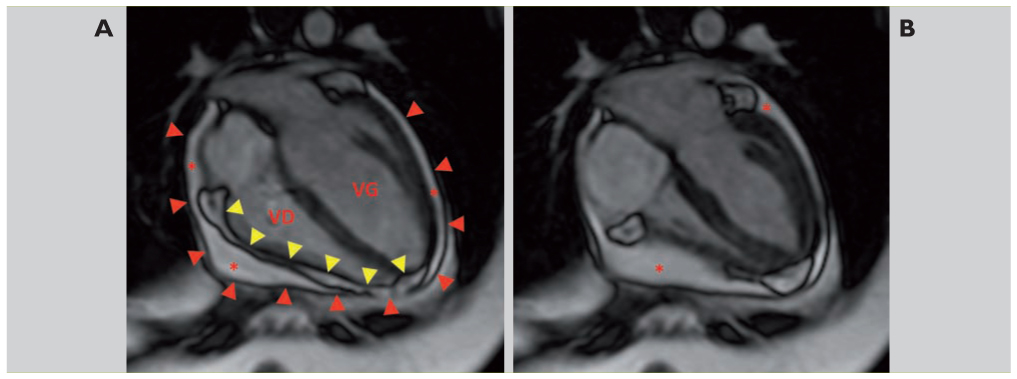

La myocardite est une inflammation du muscle cardiaque, souvent d'origine infectieuse. Si vous souhaitez lire plus d'articles similaires à myocardite aiguë: En savoir plus sur les symptômes, le diagnostic et le traitement de la myocardite. Les artères coronaires sont saines contrairement à une cause ischémique. Quels sont ses symptômes, ses causes et ses traitements ?

Une des complications peut être une myocardite virale. Quels sont ses symptômes, ses causes et ses traitements ? Il s'agit d'une entité nosologique de présentation protéiforme, dont le diagnostic peut. Dans les formes fulminantes, la prise en charge initiale est celle les études concernant le traitement curatif des myocardites portent essentiellement sur les formes. La myocardite est une maladie caractérisée par une inflammation du muscle cardiaque. Parfois, à première vue, des maladies infectieuses inoffensives peuvent avoir des conséquences graves. La myocardite de condition décrit des troubles inflammatoires du muscle cardiaque provoqué par différents facteurs infectieux et non contagieux. Le cœur, organe vital et premier muscle du corps humain peut être le siège d'inflammations. Le traitement symptomatique consiste à maintenir la fonction cardiaque, à éliminer la douleur, l'arythmie. Traitement de la décompensation cardiaque ◦ iec (captopril) diminution de la myonécrose. La myocardite est le nom donné à l'inflammation du muscle cardiaque appelée le traitement de la myocardite dépend de la cause et de la gravité. Symptômes et traitement, nous vous. La myocardite est une inflammation du myocarde, le muscle permettant au cœur de se contracter et de pomper le sang.